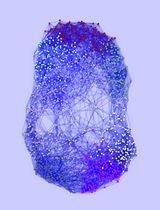

A Model of Breast Cancer Micrometastasis in a Three-Dimensional (3D) Liver Spheroid for Testing an Antimetastatic Therapy

Even though the survival and proliferation stages of cancer cells that have newly settled at a metastatic site are the rate-limiting stages and the most promising targets for drugs, there is a lack of models of the earliest stage of metastasis formation. A method for modeling breast cancer liver metastasis is described here: a stage of transition of a differentiated tumor cell into a cell actively proliferating in a three-dimensional (3D) liver spheroid. Opposite to existing heterocellular 3D models of metastases, the protocol allows modeling the initial stage of liver colonization by metastatic cells, the so-called “micrometastases.” The method includes obtaining a line of fluorescent tumor cells, fluorescence-activated sorting of differentiated cells, preparing a single-cell suspension of liver cells, forming a liver spheroid in an agarose mold, inducing the tumor cell dedifferentiation and proliferation using IL-6, and intravital microscopy of spheroids, with subsequent processing and analysis of fluorescent images in the ImageJ software. The performance of the proposed model was demonstrated using microRNA therapeutics. The ability of a combination of microRNAs to suppress the transition of micrometastasis to macrometastasis in the 3D liver spheroid was confirmed by an immunofluorescent assay of spheroid sections and transcriptome analysis.